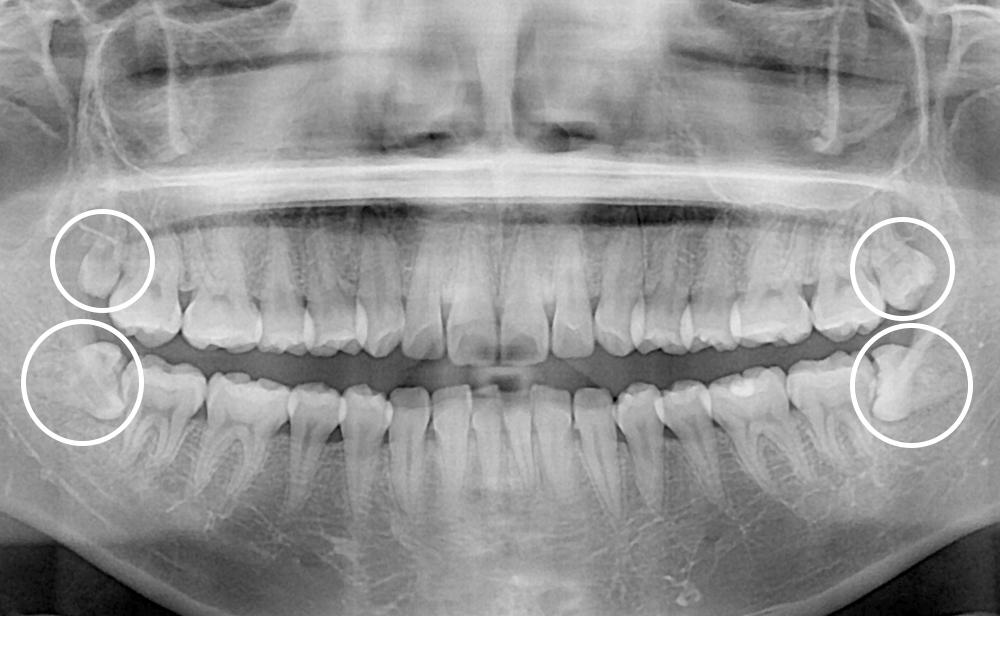

[사랑니] 매복 사랑니 발치

치료후 : 2020-04-27

세종치과는 구강악안면외과학 박사이신 원장님이 발치하는 치과입니다.